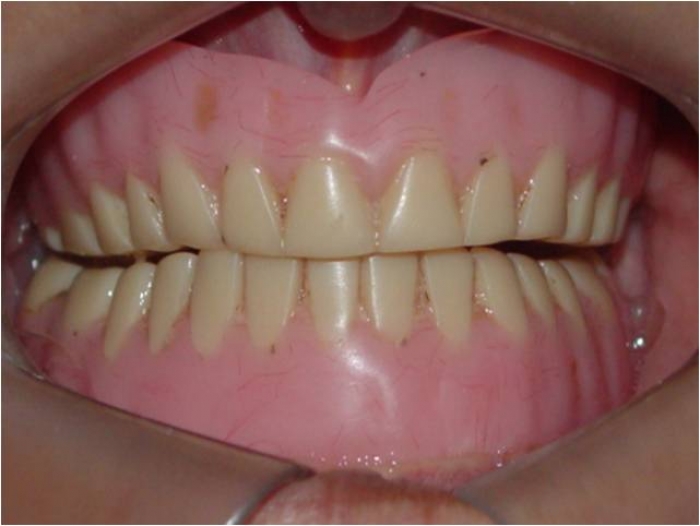

Prótese fixa inferior em resina

Sorriso final, do caso terminado em Janeiro de 2014